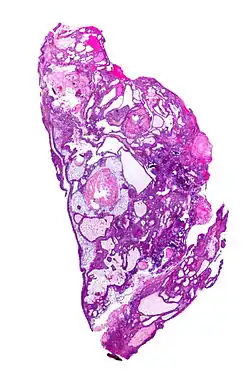

Very low magnification micrograph of an adamantinomatous craniopharyngioma. HPS stain.

• Adamantinomatous craniopharyngiomas, which resemble ameloblastomas (the most common type of odontogenic tumor), are characterized by activating CTNNB1 mutations.

In the adamantinomatous type, calcifications are visible on neuroimaging and are helpful in diagnosis.

On macroscopic examination, craniopharyngiomas are cystic or partially cystic with solid areas. On light microscopy, the cysts are seen to be lined by stratified squamous epithelium. Keratin pearls may also be seen. The cysts are usually filled with a yellow, viscous fluid rich in cholesterol crystals. Of a long list of possible symptoms, the most common presentations include headaches, growth failure, and bitemporal hemianopsia.